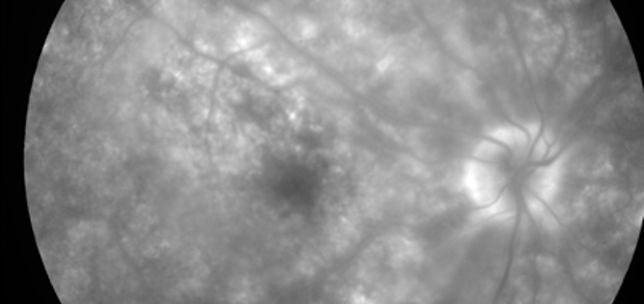

Birdshot chorioretinopathy: an important differential

Zaria Ali

Mohammed Alarbi

Salwa Abugreen

1st April 2015